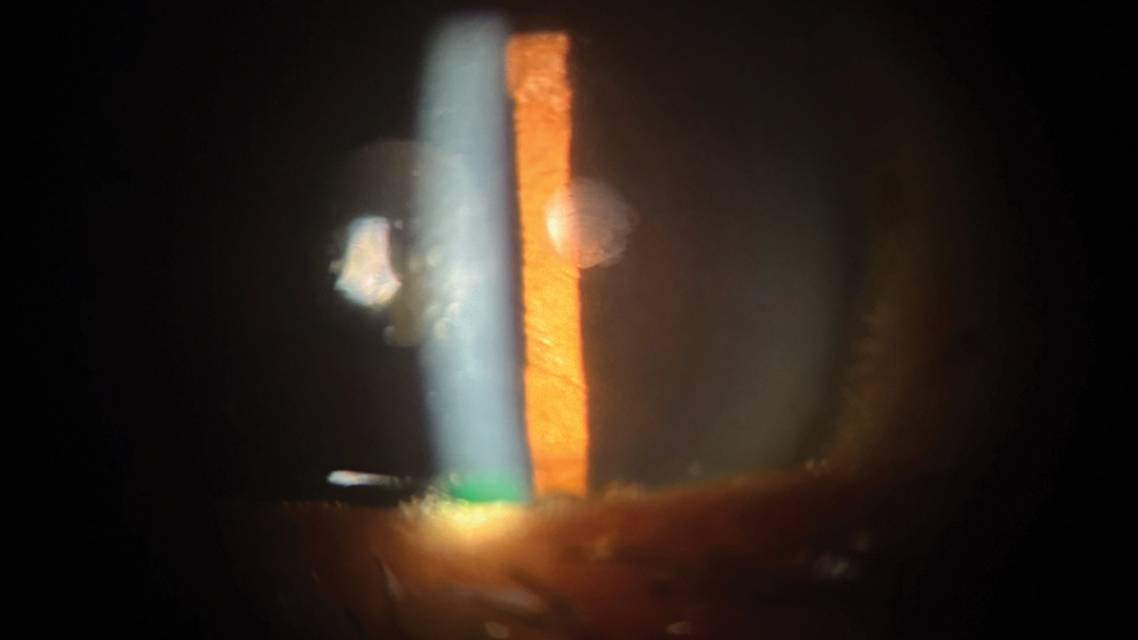

Retained lens fragments may be found in the anterior chamber, posterior chamber, vitreous cavity, or capsular bag. Nuclear fragments are yellow in color with sharp edges, whereas cortical fragments appear white and fluffy. Although most retained lens fragments are seen in the early postoperative days, in some cases, it may be decades before they are identified or pose a threat to the patient’s ocular health.2

Early recognition, material identification, and appropriate management are critical to ensure positive patient outcomes. Most retained lens fragments can be easily seen during the slit-lamp examination (Figure); however, gonioscopy and B-scan ultrasonography may allow better visualization and localization. Management typically involves surgical removal of the fragments, although cortical lens fragments may dissolve spontaneously over time. It is also necessary to control IOP and treat any ocular inflammation with topical steroids such as prednisolone acetate. Topical miotics such as pilocarpine may be considered to sequester the fragment in the anterior chamber, avoiding posterior complications.3